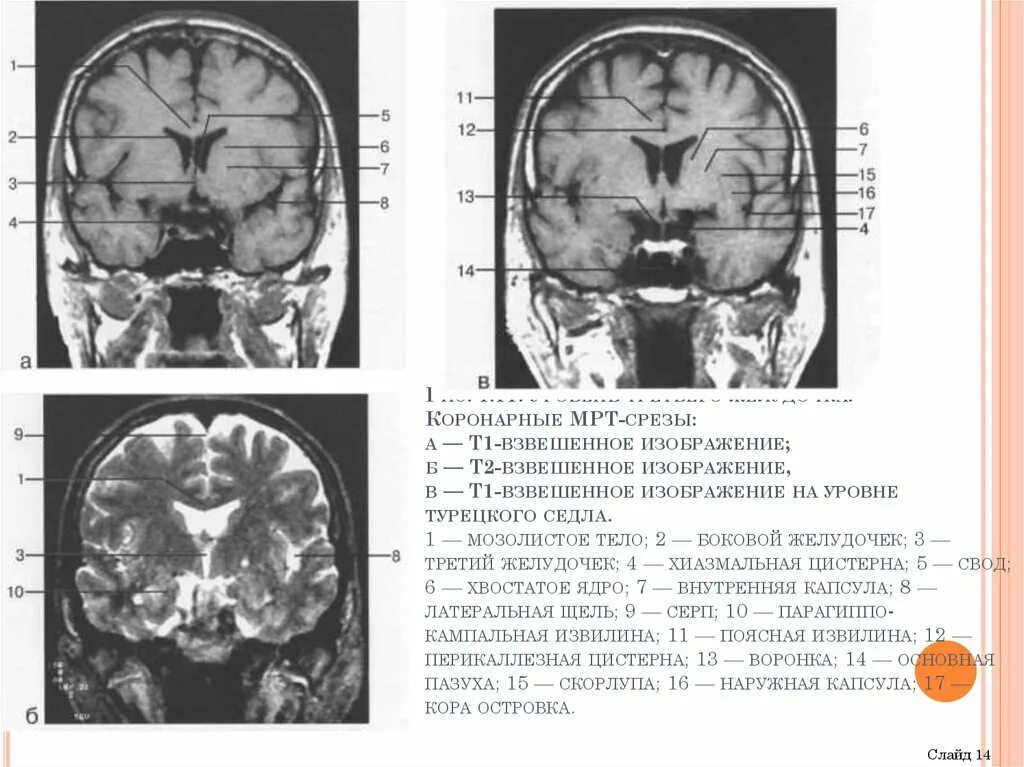

Цистерны на кт